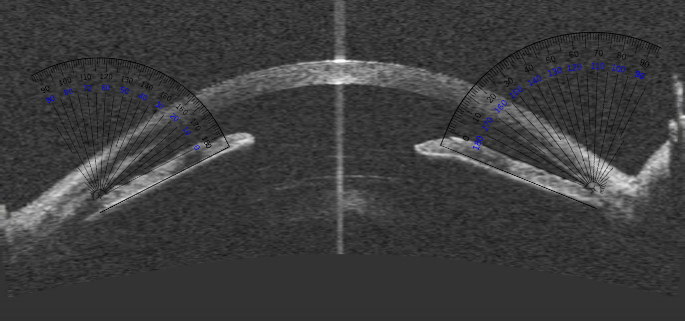

Anterior Segment OCT (AS-OCT)

AS-OCT images can also be processed for structure segmentation, measurement, and screening for angle closure using algorithms being developed.[33] Niwas et al evaluated a fully automated model to classify angle closure glaucoma from AS-OCT scans and showed an accuracy of 89.2%.[34]